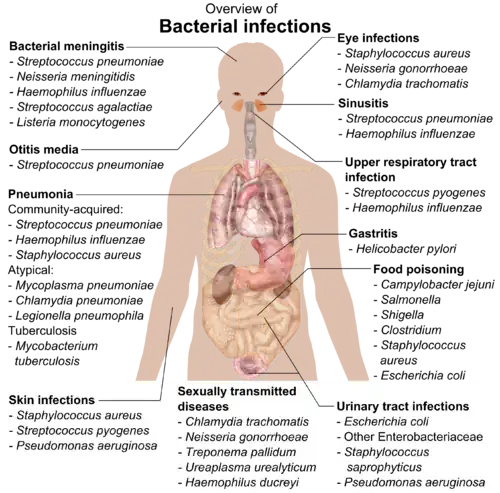

Like all animals, humans carry vast numbers (approximately 1013 to 1014) of bacteria.[8] Most are in the gut, though there are many on the skin. Most of the bacteria in and on the body are harmless or rendered so by the protective effects of the immune system, and many are beneficial,[9] particularly the ones in the gut. However, several species of bacteria are pathogenic and cause infectious diseases, including cholera, syphilis, anthrax, leprosy, tuberculosis, tetanus and bubonic plague. The most common fatal bacterial diseases are respiratory infections. Antibiotics are used to treat bacterial infections and are also used in farming, making antibiotic resistance a growing problem. Bacteria are important in sewage treatment and the breakdown of oil spills, the production of cheese and yogurt through fermentation, the recovery of gold, palladium, copper and other metals in the mining sector (biomining, bioleaching), as well as in biotechnology, and the manufacture of antibiotics and other chemicals.

If bacteria form a parasitic association with other organisms, they are classed as pathogens.[224] Pathogenic bacteria are a major cause of human death and disease and cause infections such as tetanus (caused by Clostridium tetani), typhoid fever, diphtheria, syphilis, cholera, foodborne illness, leprosy (caused by Mycobacterium leprae) and tuberculosis (caused by Mycobacterium tuberculosis).[225] A pathogenic cause for a known medical disease may only be discovered many years later, as was the case with Helicobacter pylori and peptic ulcer disease.[226] Bacterial diseases are also important in agriculture, and bacteria cause leaf spot, fire blight and wilts in plants, as well as Johne's disease, mastitis, salmonella and anthrax in farm animals.[227]

Each species of pathogen has a characteristic spectrum of interactions with its human hosts. Some organisms, such as Staphylococcus or Streptococcus, can cause skin infections, pneumonia, meningitis and sepsis, a systemic inflammatory response producing shock, massive vasodilation and death.[228] Yet these organisms are also part of the normal human flora and usually exist on the skin or in the nose without causing any disease at all. Other organisms invariably cause disease in humans, such as Rickettsia, which are obligate intracellular parasites able to grow and reproduce only within the cells of other organisms. One species of Rickettsia causes typhus, while another causes Rocky Mountain spotted fever. Chlamydia, another phylum of obligate intracellular parasites, contains species that can cause pneumonia or urinary tract infection and may be involved in coronary heart disease.[229] Some species, such as Pseudomonas aeruginosa, Burkholderia cenocepacia, and Mycobacterium avium, are opportunistic pathogens and cause disease mainly in people who are immunosuppressed or have cystic fibrosis.[230][231] Some bacteria produce toxins, which cause diseases.[232] These are endotoxins, which come from broken bacterial cells, and exotoxins, which are produced by bacteria and released into the environment.[233] The bacterium Clostridium botulinum for example, produces a powerful exotoxin that cause respiratory paralysis, and Salmonellae produce an endotoxin that causes gastroenteritis.[233] Some exotoxins can be converted to toxoids, which are used as vaccines to prevent the disease.[234]

Bacterial infections may be treated with antibiotics, which are classified as bacteriocidal if they kill bacteria or bacteriostatic if they just prevent bacterial growth. There are many types of antibiotics, and each class inhibits a process that is different in the pathogen from that found in the host. An example of how antibiotics produce selective toxicity are chloramphenicol and puromycin, which inhibit the bacterial ribosome, but not the structurally different eukaryotic ribosome.[235] Antibiotics are used both in treating human disease and in intensive farming to promote animal growth, where they may be contributing to the rapid development of antibiotic resistance in bacterial populations.[236] Infections can be prevented by antiseptic measures such as sterilising the skin prior to piercing it with the needle of a syringe, and by proper care of indwelling catheters. Surgical and dental instruments are also sterilised to prevent contamination by bacteria. Disinfectants such as bleach are used to kill bacteria or other pathogens on surfaces to prevent contamination and further reduce the risk of infection.[237]